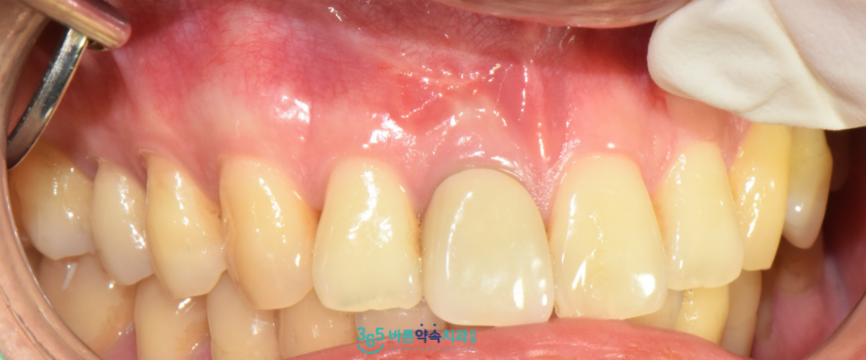

국소 마취 후

해당 부위의 잇몸을 절개하여

잇몸뼈와 치근단 주변에 있는

감염된 부위와 염증 조직을

깨끗하게 제거하였으며,

염증이 있었던 뿌리 끝을

약 2~3mm 정도 잘라낸 뒤

그 부위를 생체 적합 재료인

MTA로 역방향 충전을 시행하여

단단하게 밀봉하였는데요.

치근단 절제술 후 1주일 정도 뒤

실밥을 제거해 드렸으며

잇몸뼈 회복 상태를 확인하기 위해

파노라마와 3D CT를 촬영해 보았더니

염증이 깨끗하게 제거가 되었고

뿌리끝이 단단히 메워져 있는 것을

확인할 수 있었습니다.